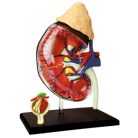

Kidney Anatomy Model

Life-sized kidney anatomy model kit. This model, and the others in the human anatomy series, are an excellent addition to any human anatomy curriculum, or science fair project.

Kidney Anatomy Model: Build your own human anatomy model of the kidney. This exceptionally detailed, 6 model contains 13 detachable, hand-painted medical education-quality parts and a display stand. Also includes illustrated assembly guide and description of the anatomy along with some fun Q&A to test your knowledge. A nice addition to the curriculum for teaching kids human anatomy or any kids science toy for fair project related to the human anatomy Model.

Collect the series and have your own human anatomy museum.

Life-sized kidney anatomy model kit. This model, and the others in the human anatomy series, are an excellent addition to any human anatomy curriculum, or science fair project. Future scientists and doctors study all the features of the human kidney and how to recognize its many sections thanks to this accurate model. The detachable pieces allow them to construct it themselves for a better understanding.

Visual and sensory learners benefit a lot from the anatomy models as they are able to touch, feel, and look closely at the model. In-home learning settings where one can’t enjoy access to a full science lab, one can buy these models for a detailed and comprehensive learning experience.

These models are of exceptional quality and provide detailed information about the functioning of the various body parts. For advanced and higher-level medical teaching such anatomy models are the best.

The front half of the kidney is removable to enable demonstration of the cortex medulla and vessels for teaching about the human kidney. The renal pelvis of the kidney is also displayed. 20 important structures of the human kidney are included in the anatomy key. The kidney with adrenal gland model comes on the stand. A life-size kidney anatomy model with an adrenal gland has been sectioned to reveal the inner anatomy. The model shows the adrenal gland, renal and adrenal vessels and the upper portion of the ureter, and the inner anatomy includes the cortex medulla, vessels and renal pelvis.

A good value model is ideal for teaching renal anatomy at a basic level. The kidney model comes on a stand and is made of slightly pliable plastic. positions and are removable from the kidneys. The model features many anatomical details of the kidneys and rear organs. The kidneys are a pair of bean-shaped organs on either side of your spine, below your ribs and behind your belly. Each kidney is about 4 or 5 inches long, roughly the size of a large fist.